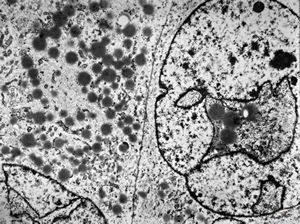

M,56y. | amyloidosis - tendon